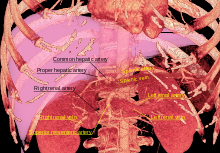

Blood supply

The kidneys receive blood from the renal arteries, left and right, which branch directly from the abdominal aorta. Despite their relatively small size, the kidneys receive approximately 20% of the cardiac output.

Each renal artery branches into segmental arteries, dividing further into interlobar arteries which penetrate the renal capsule and extend through the renal columns between the renal pyramids. The interlobar arteries then supply blood to the arcuate arteries that run through the boundary of the cortex and the medulla. Each arcuate artery supplies several interlobular arteries that feed into the afferent arterioles that supply the glomeruli.

- Renal arteries and their branches

The renal artery enters into the kidney at the level of first lumbar vertebra just below the superior mesenteric artery. As it enters the kidney it divides into branches: first the segmental artery, which divides into 2 or 3 lobar arteries, then further divides into interlobar arteries, which further divide into the arcuate artery which leads into the interlobular artery, which form afferent arterioles. The afferent arterioles form the glomerulus (network of capillaries closed in Bowman's capsule). From here, efferent arterioles leaves the glomerulus and divide into peritubular capillaries, which drain into the interlobular veins and then into arcuate vein and then into interlobar vein, which runs into lobar vein, which opens into the segmental vein and which drains into the renal vein, and then from it blood moves into the inferior vena cava.